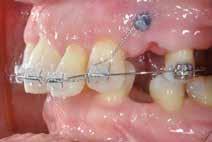

Objektivt anbefales behandling af det dybe bid, som ubehandlet forventes at forværres yderligere over tid. Patienten har ønske om behandling med æstetisk ortodontisk apparatur, alignere, og det vurderes muligt at behandle malokklusionen med alignere. Dog anbefales det generelt, at alignere undgås eller benyttes med væsentlige modifikationer af alignerens retention ved tandmobilitet, da dette ellers kan medføre jiggling, når aligneren tages af og på mange gange dagligt. På den anden side er der nogen evidens for, at alignerbehandling er associeret med bedre renhold og parodontal sundhed sammenlignet med fast apparatur (16).

Der planlægges alignerbehandling af begge kæber med intrusion af 1+1 og 2,1-1,2, nivellering af trangstilling UK med interproksimal reduktion (IPR) (Fig. 2 A, B) og senere IPR OK for reduktion af dark triangles mellem incisiverne efter nivellering. Patienten instrueres i at benytte alignere 20-22 timer/ dag med alignerskift hver 7. dag, og patienten ses hver 3.-8. uge under forløbet. Den første alignerserie består af 16 alignere for nivellering OK/UK og IPR i UK (Fig. 2). Efter denne serie planlægges IPR mellem incisiverne i OK for reduktion af dark triangles (Fig. 3) samt yderligere intrusion af OK og UK-fronten i 12 refinement-alignere. Patienten udviser god kooperation og er meget tilfreds med alignerapparaturet, som er mindre synligt end det faste apparatur (Fig. 4).

Behandlingen afsluttes med yderligere refinement-alignere for finindstilling af okklusionen, og efter 11 måneders ortodontisk behandling er der opnået normale relationer i alle tre